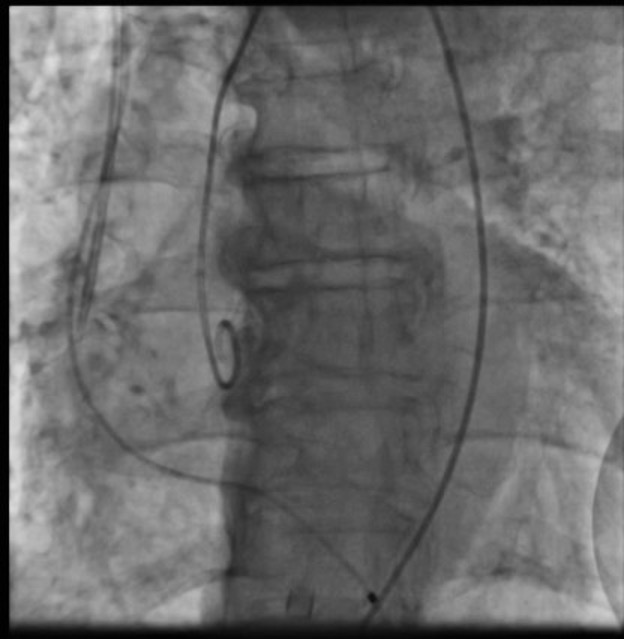

The patient was taken up for TAVR via a left common femoral artery (CFA) approach. The aortic valve was crossed (Figure 1A), and pre-dilatation was done using an 18-mm x 40-mm Mammoth balloon catheter (Meril Life Sciences) (Figure 1B). A 24.5-mm Myval transaortic valve (Meril Life Sciences) was introduced inside a Python expandable introducer sheath (Meril Life Sciences). However, the device could not be negotiated in the distal external iliac artery (EIA) due to calcium. The arrow in Figure 2A shows calcium in the distal EIA. The artery forceps depicts a marker for the distal end of the Python sheath. The sheath was withdrawn in the distal EIA; right CFA puncture was done and a 7F crossover sheath was placed. Intravascular lithotripsy (IVL) was done using a 7-mm x 60-mm IVL balloon; 30 pulses at 4 atm followed by 30 pulses at 6 atm were given (Figure 2B).